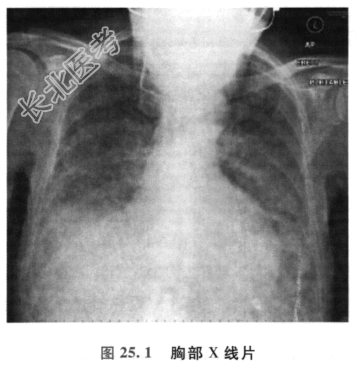

患者的胸部X线检查结果如图25.1所示